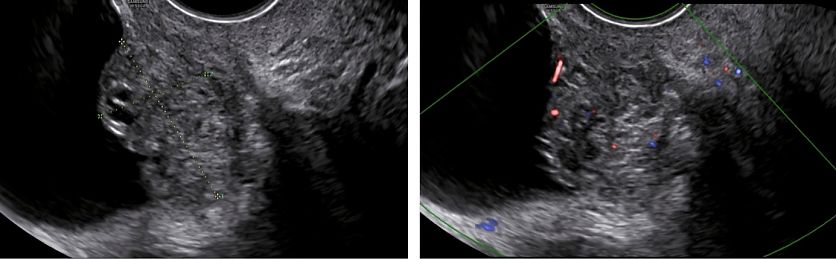

Bladder

The bladder is the most affected organ in cases of DE of the urinary tract. Lesions typically arise from the posterior bladder wall or dome (Figures 9–12), often within the detrusor layer. On TVS, these appear as hypoechoic nodules, sometimes with posterior acoustic shadowing. The lesions can be intramural or transmural, and they may protrude into the bladder lumen (Figures 10–12). Optimal bladder filling is essential for assessing wall integrity and nodule extent. The lesion should be evaluated in three orthogonal planes and its maximal dimensions should be measured, as well as the distance to the ureteral orifices if they are visible.5

Color Doppler can help distinguish between fibrotic and vascularized lesions (Figure 12). When ultrasound findings are ambiguous, or when the nodule is situated cranially, transabdominal ultrasound or MRI may be used as complementary tools.31,3

12

Typical appearance of a bladder endometriotic nodule: hypoechoic, irregular lesion protruding into the bladder wall. On color doppler, it shows moderate vascularization.